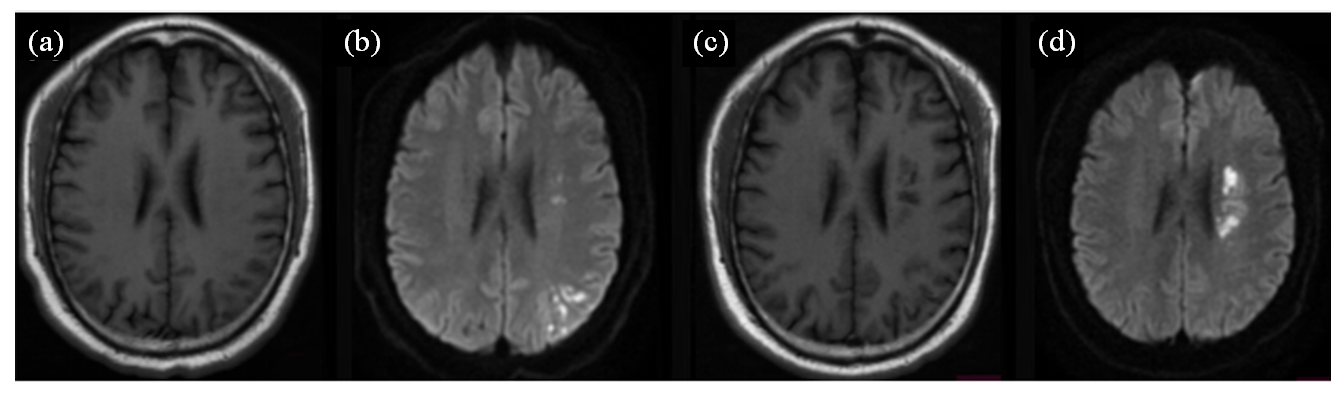

为了探讨基于磁共振弥散加权成像(MR-DWI)的急性脑梗塞患者影像解剖学特点与患者复发的相关性,本文回顾性分析了符合纳排标准的211例经临床证实的急性脑梗塞患者的临床资料和MR资料,计数病灶个数以及受累脑供血区个数,测量梗塞灶总面积和头皮下脂肪面积;分析患者一年内复发、未复发的情况与上述数据的相关性.结果表明急性脑梗塞复发组和未复发组间,病灶个数、受累供血区个数的差异有统计学意义(p<0.05);两组间,轴位图像上病灶的总面积、头皮下脂肪面积的差异无统计学意义(p>0.05).由此可见急性脑梗塞患者MR-DWI图像上的病灶个数、受累脑供血区个数是患者一年内是否复发的主要影响因素,该研究可为临床医师对患者进行个体性治疗和预后评价提供影像学依据.

To explore the correlation between the imaging anatomical characteristics of acute cerebral infarction patients based on magnetic resonance diffusion-weighted imaging (MR-DWI) and the recurrence of patients. This study retrospectively analyzed the clinical data and MR data of 211 patients with acute cerebral infarction confirmed clinically and meeting the inclusion and exclusion criteria. The number of lesions and the number of involved cerebral blood supply areas were counted, and the total area of infarction and the area of subcutaneous fat were measured. The correlation between the recurrence and non-recurrence of patients within one year and the above data was analyzed. The results showed that there was a statistically significant difference in the number of lesions and the number of involved blood supply areas between the recurrence and non-recurrence groups of acute cerebral infarction (p < 0.05); there was no statistically significant difference in the total area of lesions on axial images and the area of subcutaneous fat between the two groups (p > 0.05). Therefore, it is concluded that the number of lesions and the number of involved cerebral blood supply areas on MR-DWI images of acute cerebral infarction patients are the main influencing factors for recurrence within one year. This study can provide imaging evidence for clinicians to conduct individualized treatment and prognosis evaluation of patients.